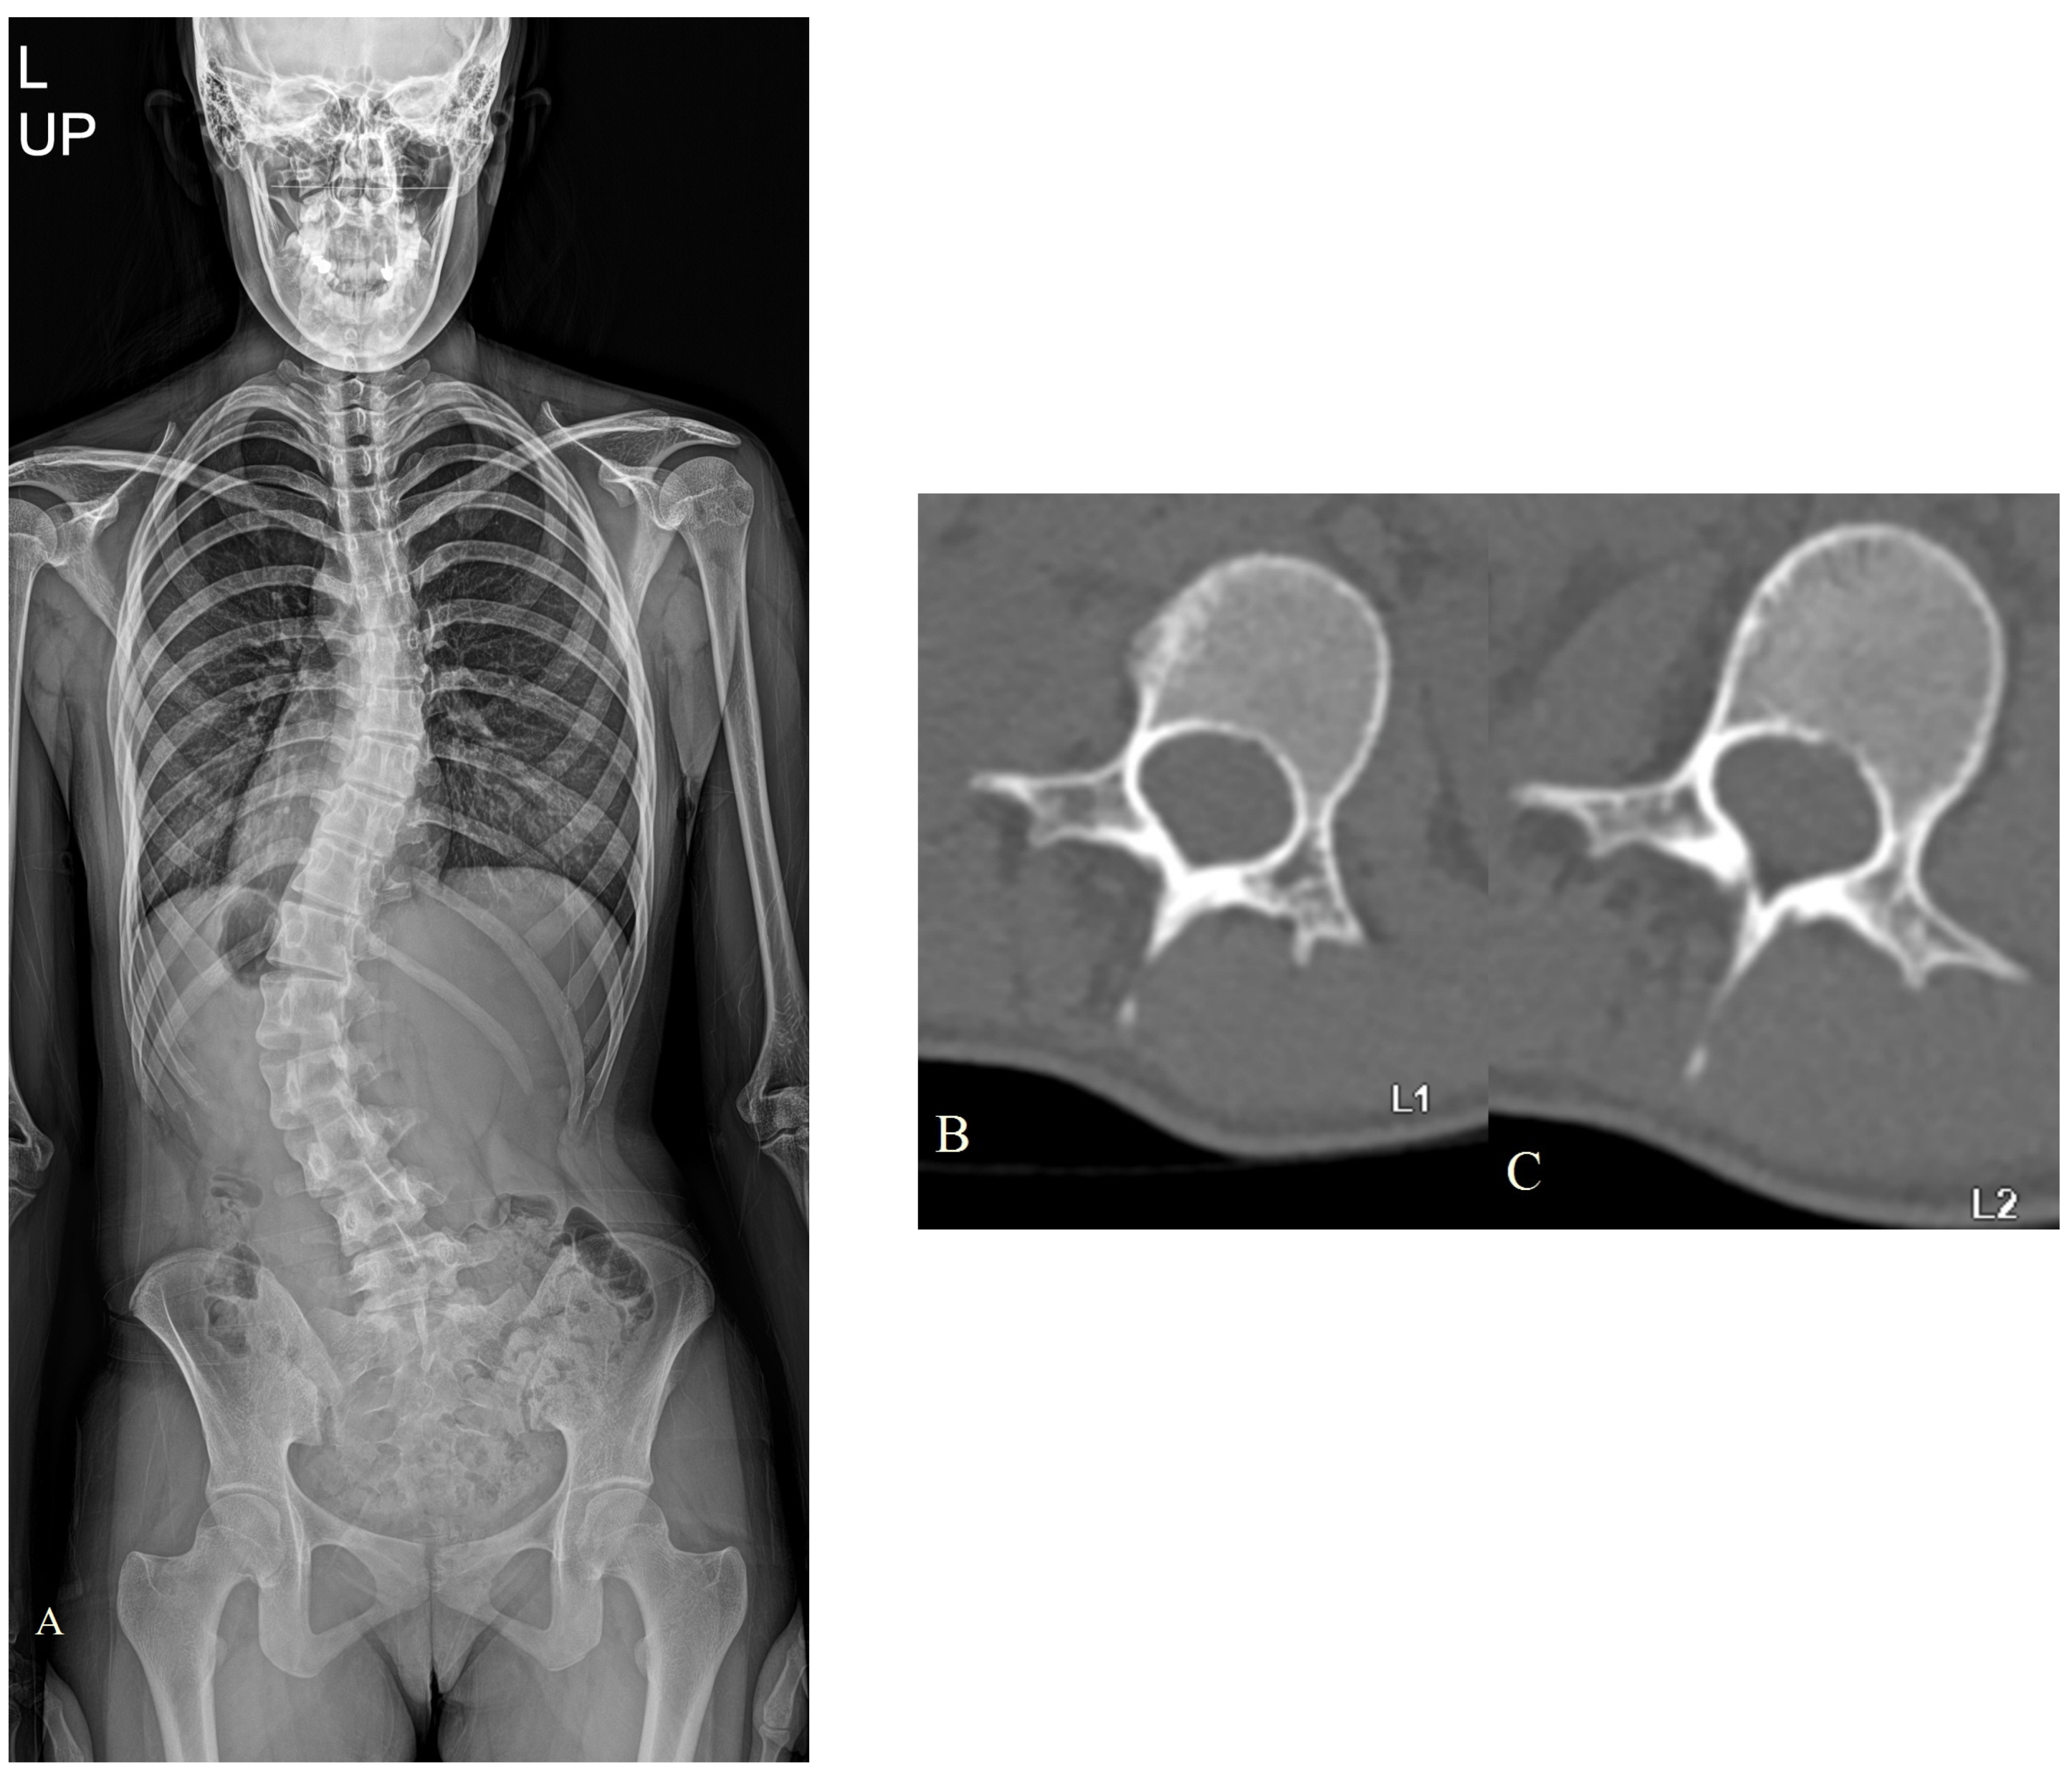

| C | 13/M | AIS | L1 | 32 | 60 | 45 | 51 | 1 | 5C |

| L | 10/F | Marfan scoliosis | L1 | 28 | 71 | 50 | 41 | ||

| L2 | 22 | ||||||||